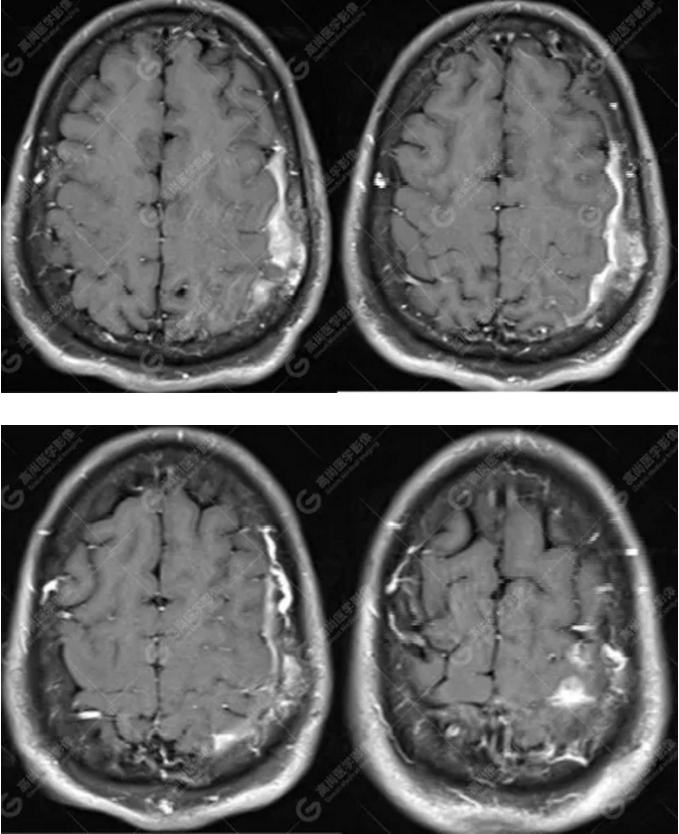

中年男性,反復(fù)出現(xiàn)手腳抽搐、暈倒伴意識(shí)喪失3年余,臨床擬診癲癇發(fā)作,后到高尚醫(yī)學(xué)影像診斷中心行MR檢查。

MR圖像

左側(cè)額頂部顱骨骨質(zhì)破壞并相鄰硬腦膜增厚強(qiáng)化,考慮Rosai Dorfman病(RDD)可能,需與朗格漢斯細(xì)胞組織細(xì)胞增生癥鑒別。

本病多累及淋巴結(jié),原發(fā)于中樞神經(jīng)系統(tǒng)而無(wú)身體其他部位淋巴結(jié)腫大者罕見,低于4%。顱內(nèi)RDD好發(fā)于中年男性,多表現(xiàn)為顱內(nèi)腦實(shí)質(zhì)外的單發(fā)或多發(fā)腫塊,好發(fā)于大腦凸面、鐮旁、鞍區(qū)及海綿竇旁,絕大多數(shù)病例都與硬腦膜密切相關(guān),腫塊多位于硬腦膜外或硬腦膜下。

腦膜瘤起源于蛛網(wǎng)膜細(xì)胞或蛛網(wǎng)膜帽狀細(xì)胞, 常發(fā)于中老年,女性好發(fā),形態(tài)上多呈半圓或橢圓型隆起的顱內(nèi)腦外病變,典型MRI影像表現(xiàn)為在 T1WI及T2WI等信號(hào),但腦膜瘤病理亞型較多,依據(jù)其組織成分不同 T2WI 信號(hào)可有改變;

總之,顱內(nèi)RDD是一種罕見的硬腦膜良性病變,若 MRI發(fā)現(xiàn)顱內(nèi)基于硬腦膜扁平或匍匐生長(zhǎng)的孤立或者多發(fā)腫塊,CT 檢查未見鈣化,而MR檢查T2WI及 DWI呈低信號(hào),增強(qiáng)明顯均勻強(qiáng)化,應(yīng)考慮到 RDD 的可能。